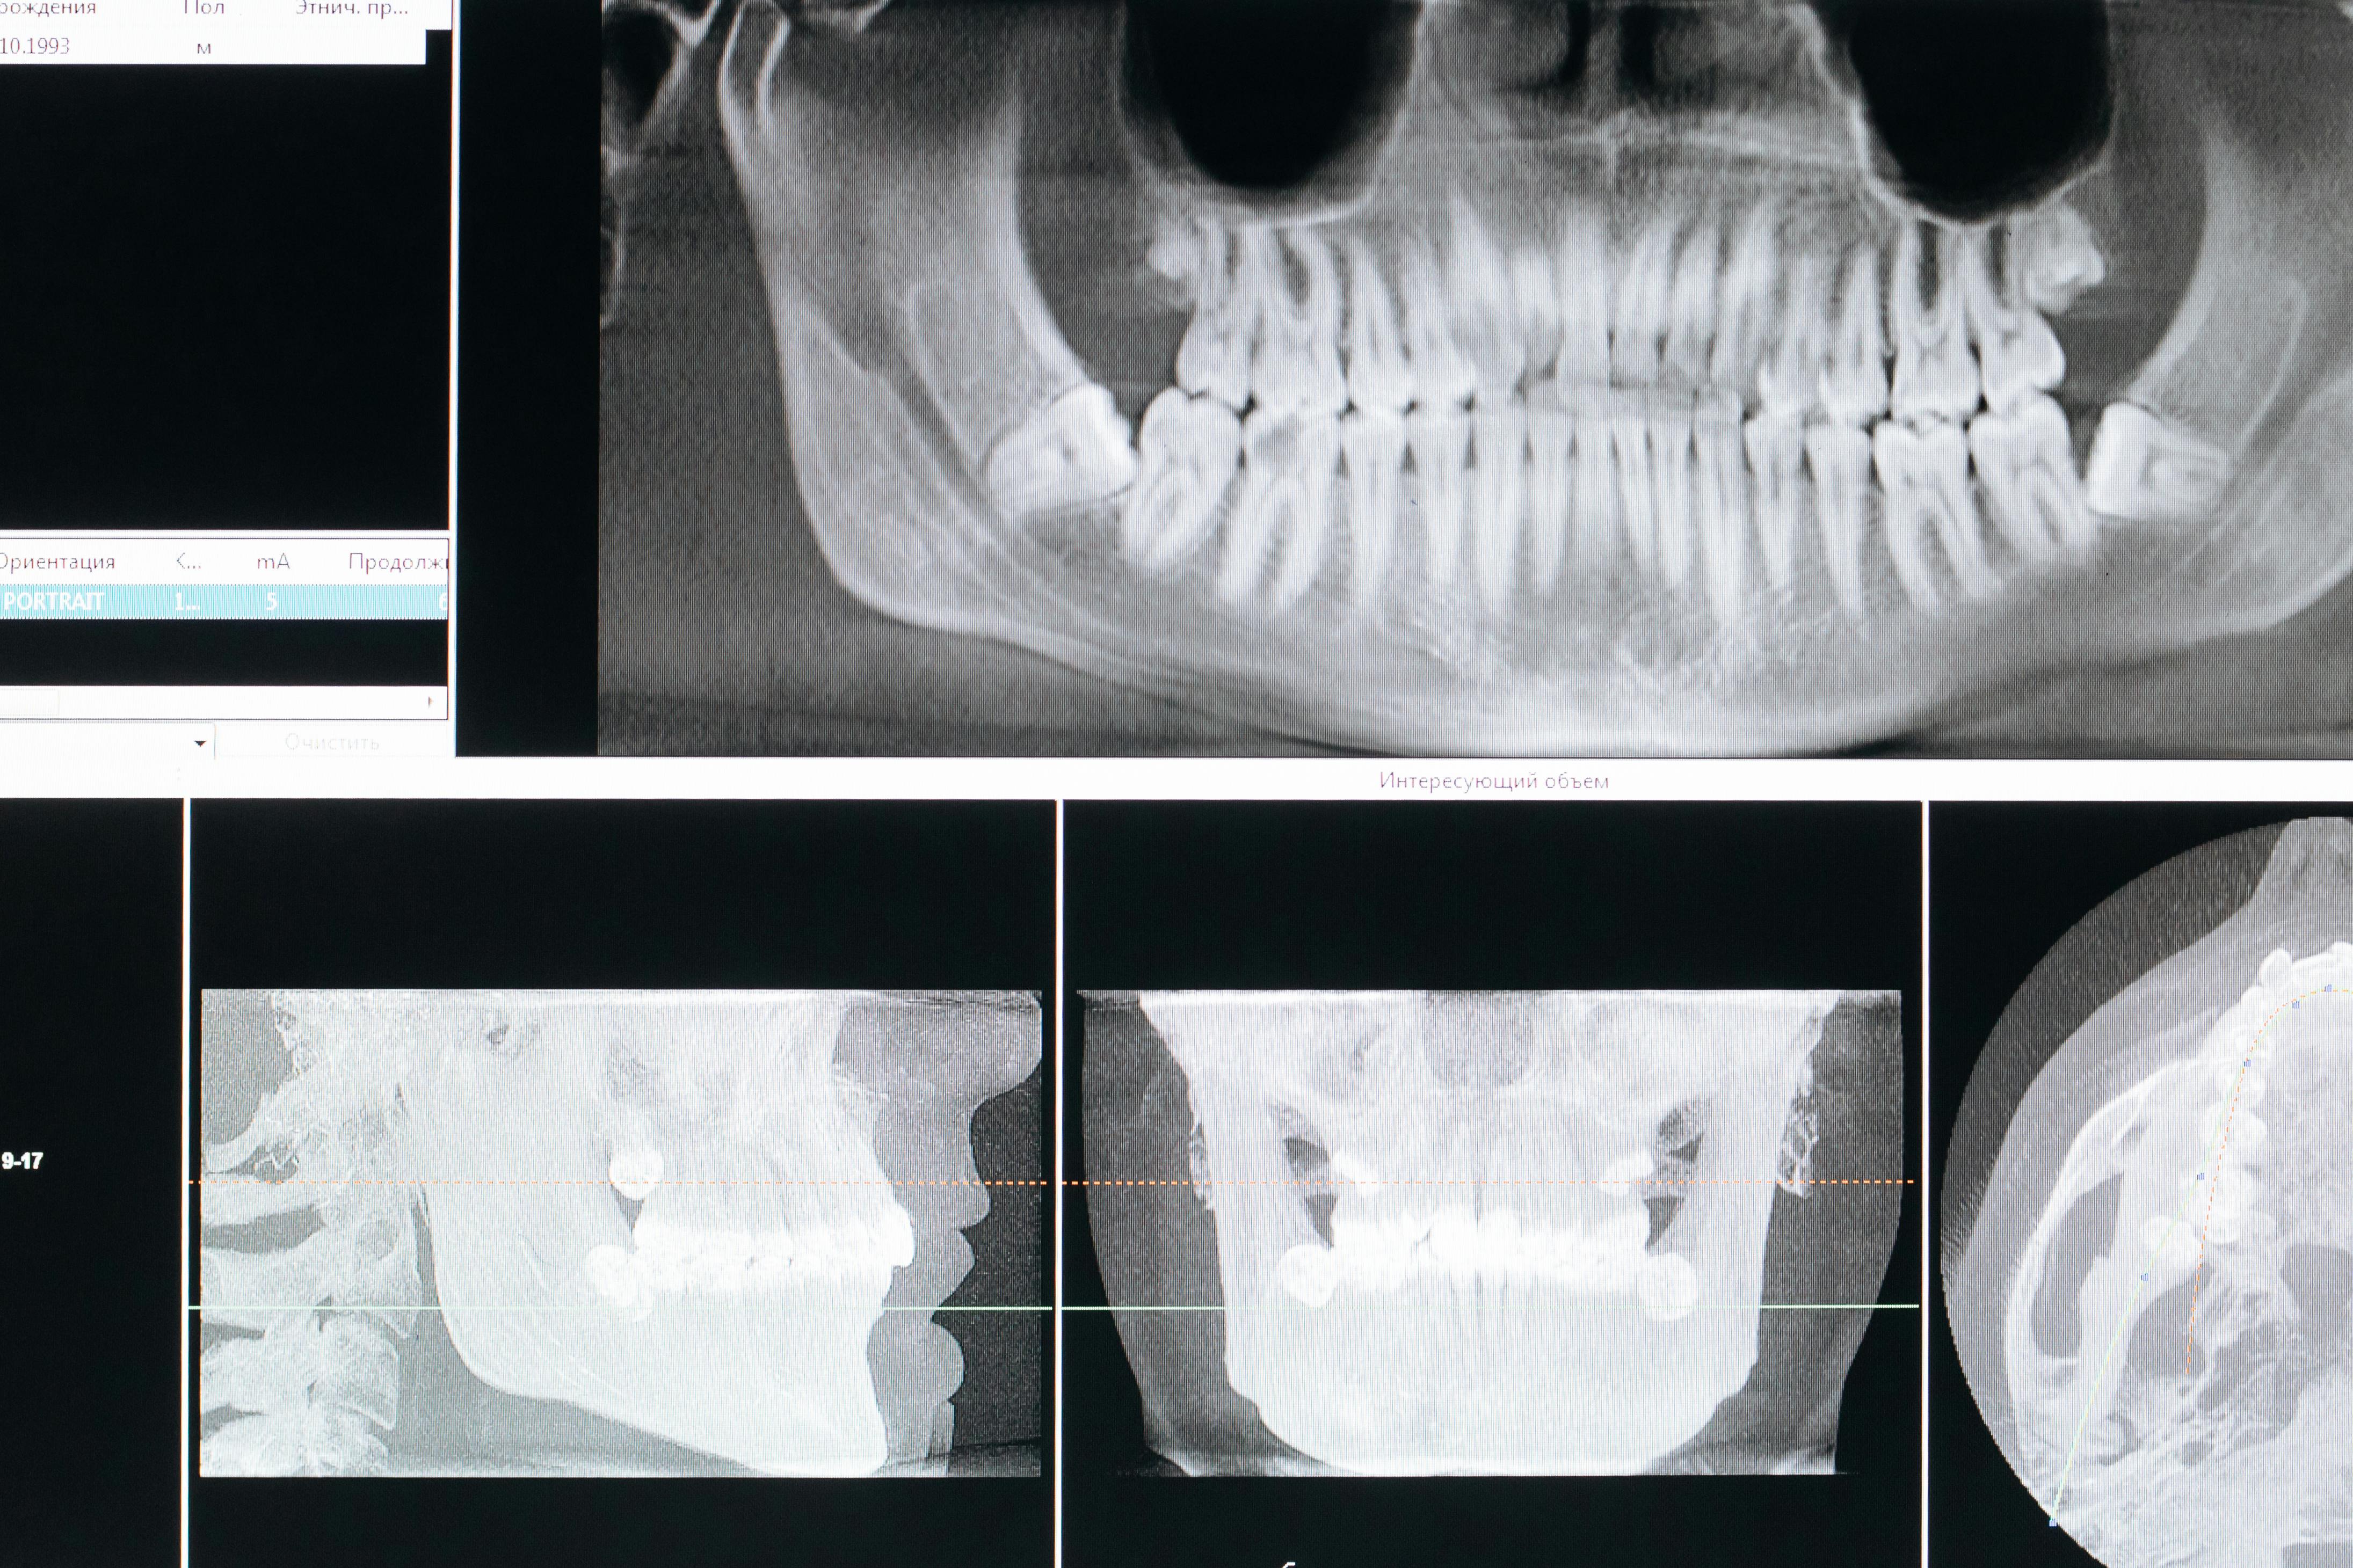

Для вирішення питання про деталі хірургічного етапу лікування проводиться комп'ютерна томографія (3D-знімок), по якій хірург визначає якість і кількість кісткової тканини, потребу в додаткових операціях, розмір необхідних імплантатів. Подалі знімається шаблон щелепи, який відправляється у лабораторію.